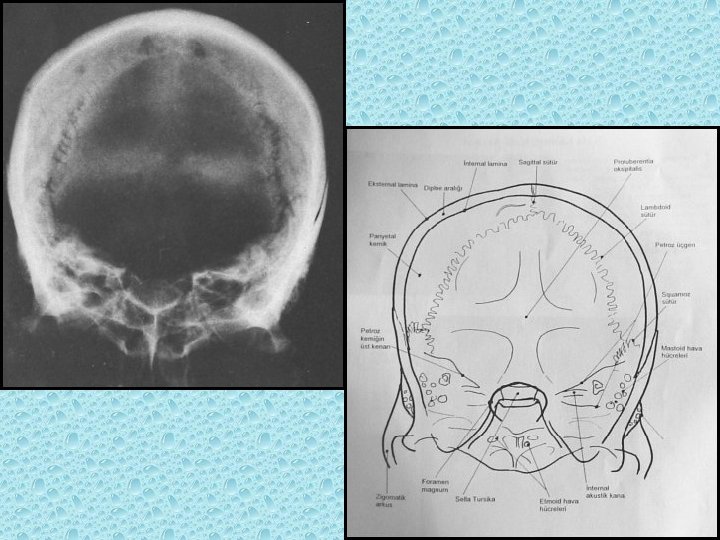

BAŞ-YÜZ RADYOLOJİK ANATOMİSİ

KRANYAL KEMİKLER • • • Paryetal (2) Frontal Oksipitai Temporal (2) Sfenoid Etmoid

KRANYAL SÜTÜRLER • Koronal (Paryetal-frontal arasında) • Sagital (iki paryetal arasında) • Lambdoid (paryetal, temporal ile oksipital arasında) • Skuamoz (Paryetal-temporal arasında)